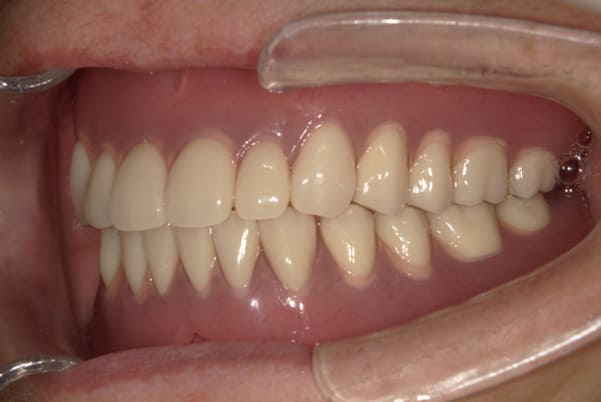

症例レポート[CASE.03]

入れ歯がガタつく、

見た目も改善したい

- 性別・年齢

- 女性(50代)

- 主訴

- 入れ歯がガタつく、何度調整してもよくならない。できれば見た目も良くしたい。

- 治療

-

- 上顎精密金属床部分入れ歯

- ジルコニアクラウン3歯

- 治療期間

- 約4か月間

- 費用

- 上顎精密金属床部分入れ歯:55万円

(ミリング、ラベット加工込み) - ジルコニアクラウン:11万円×3歯

合計:88万円(税込)

上あごに接する入れ歯に違和感がありになっていたとのことで、プラスチックが大きく削られた入れ歯をされていました。

そのため入れ歯の安定が悪く、お食事の際に入れ歯が動き、がたつきを感じられている状態でした。

前歯にバネにより見た目の問題も抱えておられました。

かみ合わせが低くなった歯を本来の高さに戻し、保険では使用できない歯に負担のかかりずらいバネで、歯の保存、審美性を確保しました。

前歯にバネを設定せず、見えない奥歯に維持力をもたせたバネを用い、またバネのかかる歯の負担軽減を目的に、被せ物は繋げることで強度を増す設計とすることで、入れ歯が動かずガタつき、審美性不良が解消されました。

部分入れ歯と対合歯

入れ歯を修理する中で、入れ歯の上あごの接触面積ではなく、厚みに対しての違和感と診断し、薄い金属を用いた従来の厚みを1/3程度にした入れ歯にすることにより違和感は消失しました。